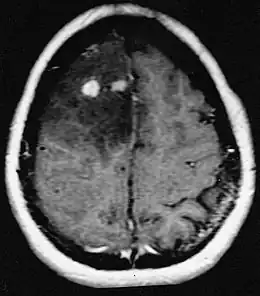

Astrocytome anaplasique

L'astrocytome anaplasique est une tumeur maligne (grade III selon la classification de l'OMS). Il se développe à partir des astrocytes (cellules nerveuses en forme d'étoile)[1]. Il est classé avec les glioblastomes multiformes et les oligodendrogliomes parmi les gliomes malins.

Beaucoup moins fréquents que les glioblastomes, il survient à tout âge mais le plus souvent entre 40 et 60 ans et plus fréquemment chez l'homme. La médiane de survie peut être de l'ordre de trois ans. On ne connaît pas les causes de cette maladie. La tumeur siège le plus souvent au niveau de la substance blanche. Leur prolifération cellulaire est importante et ils peuvent évoluer rapidement vers un glioblastome.